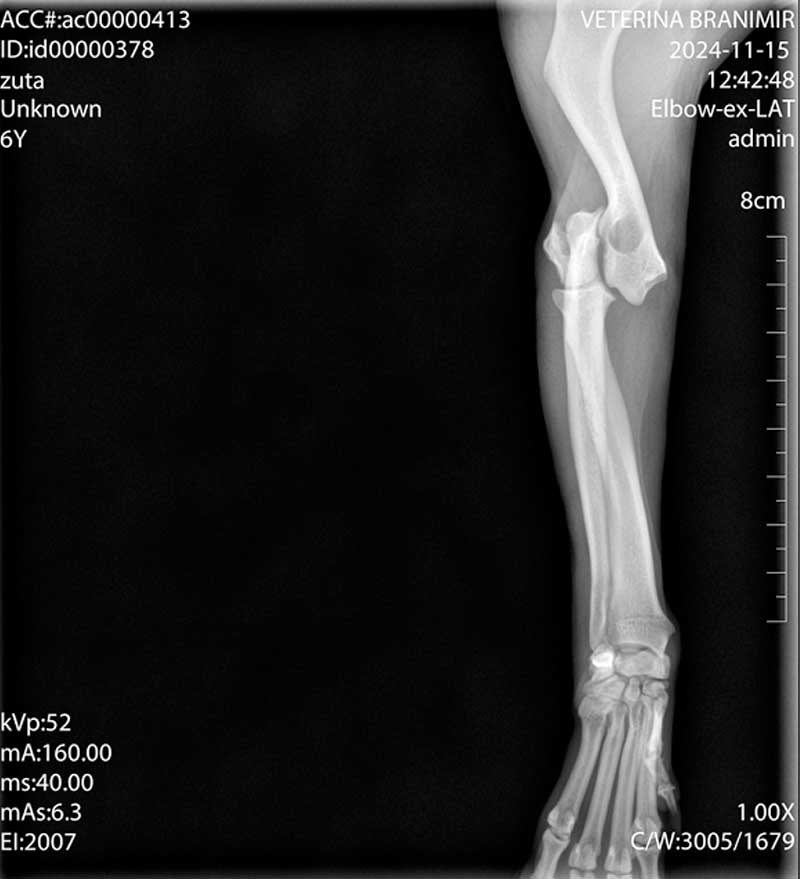

Dijagnoza se postavlja rendgenskim snimkama koje pokazuju lokaciju i tip prijeloma.

Liječenje može biti konzervativno, pomoću gipsa ili udlage, ili kirurško, uključujući pločice, vijke, čavle ili vanjsku fiksaciju.